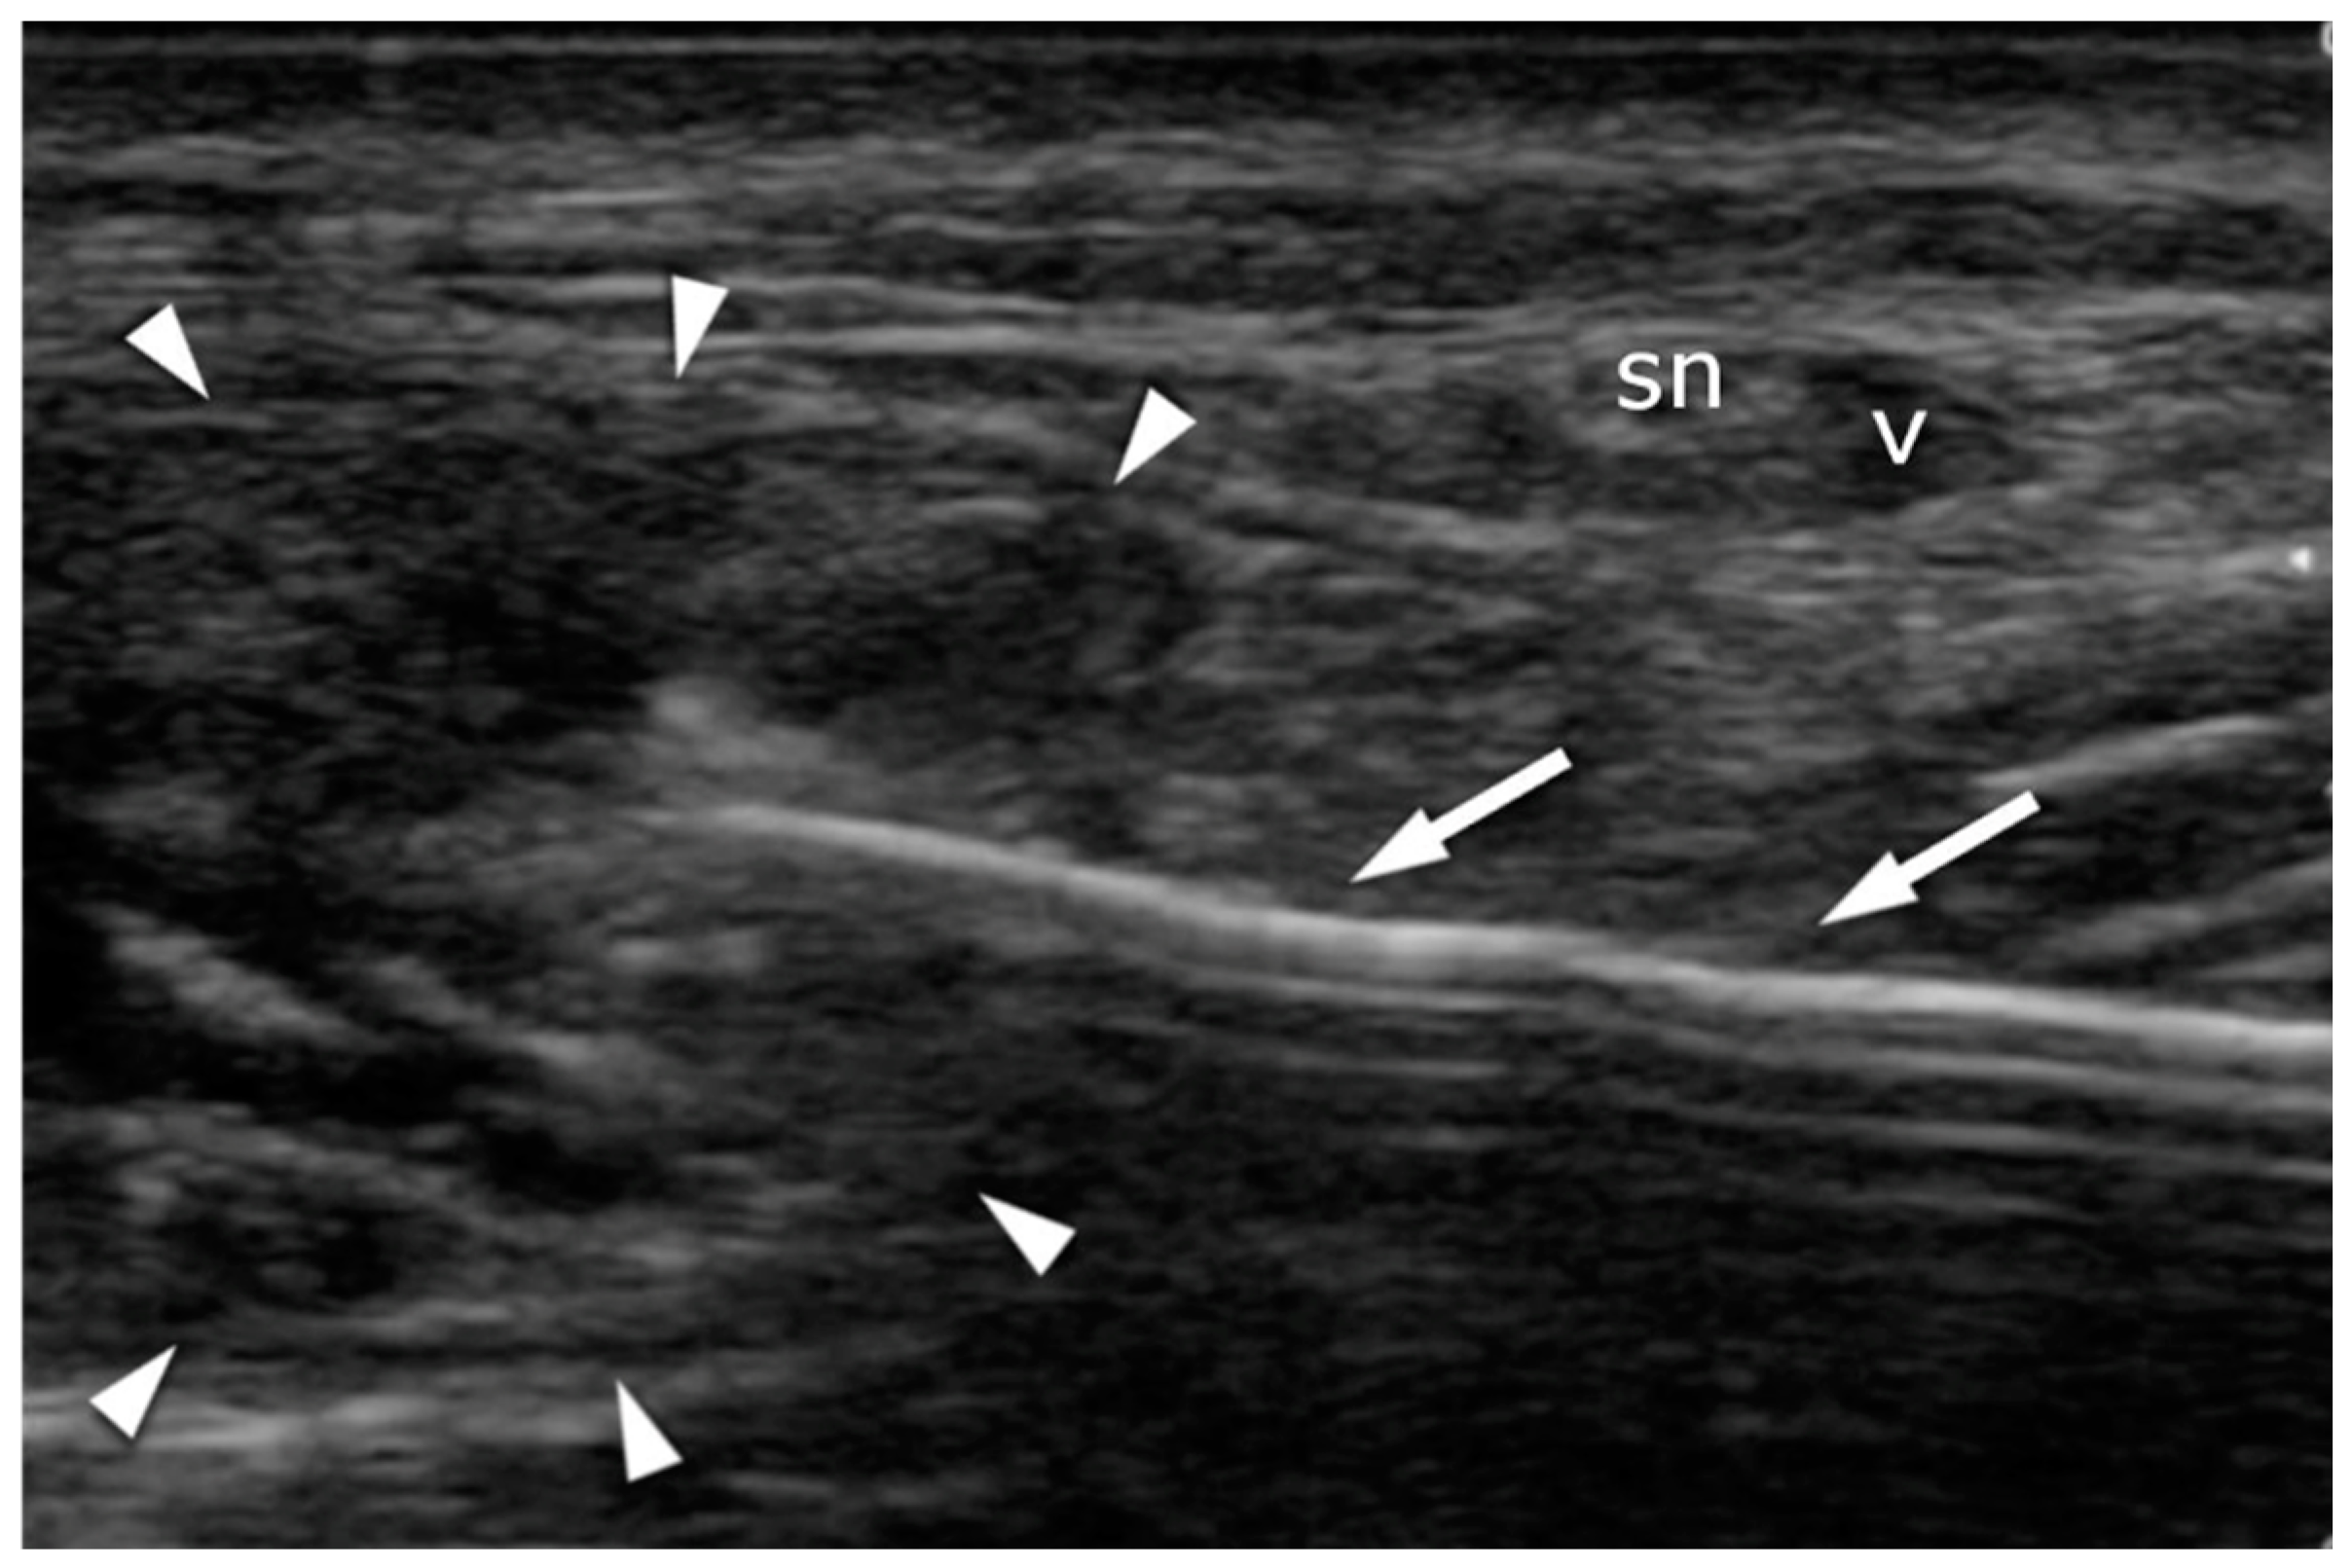

Figure 6.

Achilles tendon (arrowheads) suturing: transverse plane. The needle (arrows) is introduced under US guidance in order to avoid contact with the sural nerve (sn) and the vein (v).